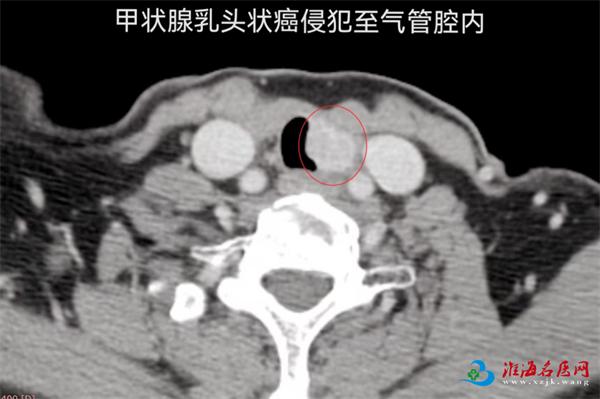

2019年,张女士因甲状腺乳头状癌接受了甲状腺全切术及碘-131治疗。2022年,因颈部淋巴结转移再次手术,术后长期口服靶向药物控制病情。2025年10月,她开始出现咯血症状,检查发现肿瘤在左侧气管旁复发,并已侵犯气管壁,这正是导致她咯血的原因。由于患者高龄、既往多次手术及放疗导致颈部解剖结构复杂、粘连严重,手术重建气道的风险极高,治疗一度陷入困境。

抱着希望,张女士与家人走进了徐州市中心医院甲状腺与疝外科门诊。面对高龄、已多次手术并接受过放疗的张女士,摆在治疗团队面前的是一系列棘手难题:颈部正常解剖结构早已改变,组织粘连严重;肿瘤紧贴气管并已侵犯气管壁,单纯局部切除已无济于事。而一旦涉及气管切除,就意味着要进行气管的“断肢再接”——即对病变段气管实施袖状切除+上下段吻合,这在甲状腺外科领域属于顶尖难度的手术。